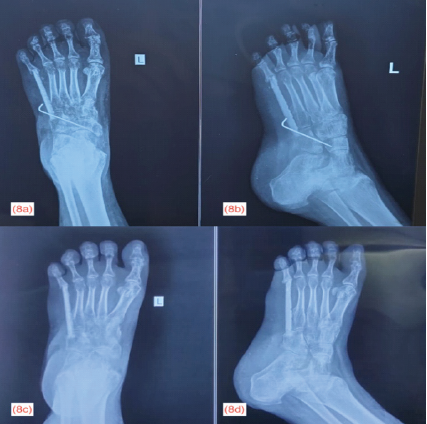

The definitive histopathological report was GCT with secondary Aneurysmal Bone Cyst changes. The specimen showed classic features: Osteoclast-like giant cells uniformly distributed in a background of mononuclear stromal cells with no nuclear atypia. Based on the above clinical, radiological and histopathological findings, the Enneking staging for this lesion is Stage 2 (Active). The post-operative period was uneventful and the patient was discharged on the 10th post-operative day. A below-knee cast was applied for 2 months to protect the graft and fixation and she was mobilized non-weight bearing. The distal K-wire was removed due to loosening at the end of the 2nd month. Below-knee cast continued for another 1 month and the proximal K-wire was removed at the end of the 3rd month. Fig. 8 shows the follow-up radiograph taken at the 2nd and 5th post-operative months.

Figure 8: Second month follow-up anteroposterior (a) and oblique view (b) radiograph of left foot showing K-wire in situ with disuse osteoporosis; 5th month follow-up anteroposterior (c) and oblique view (d) radiograph of left foot showing improvement in bone density following mobilization exercises